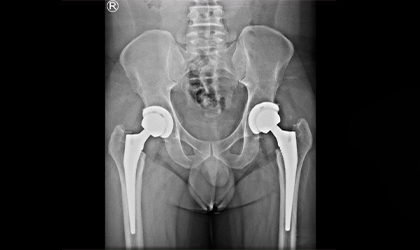

Hip Arthroscopy Case Study

Bilateral Hip Recovery

This 34 year old medical representative had avascular necrosis with collapse of both her hips